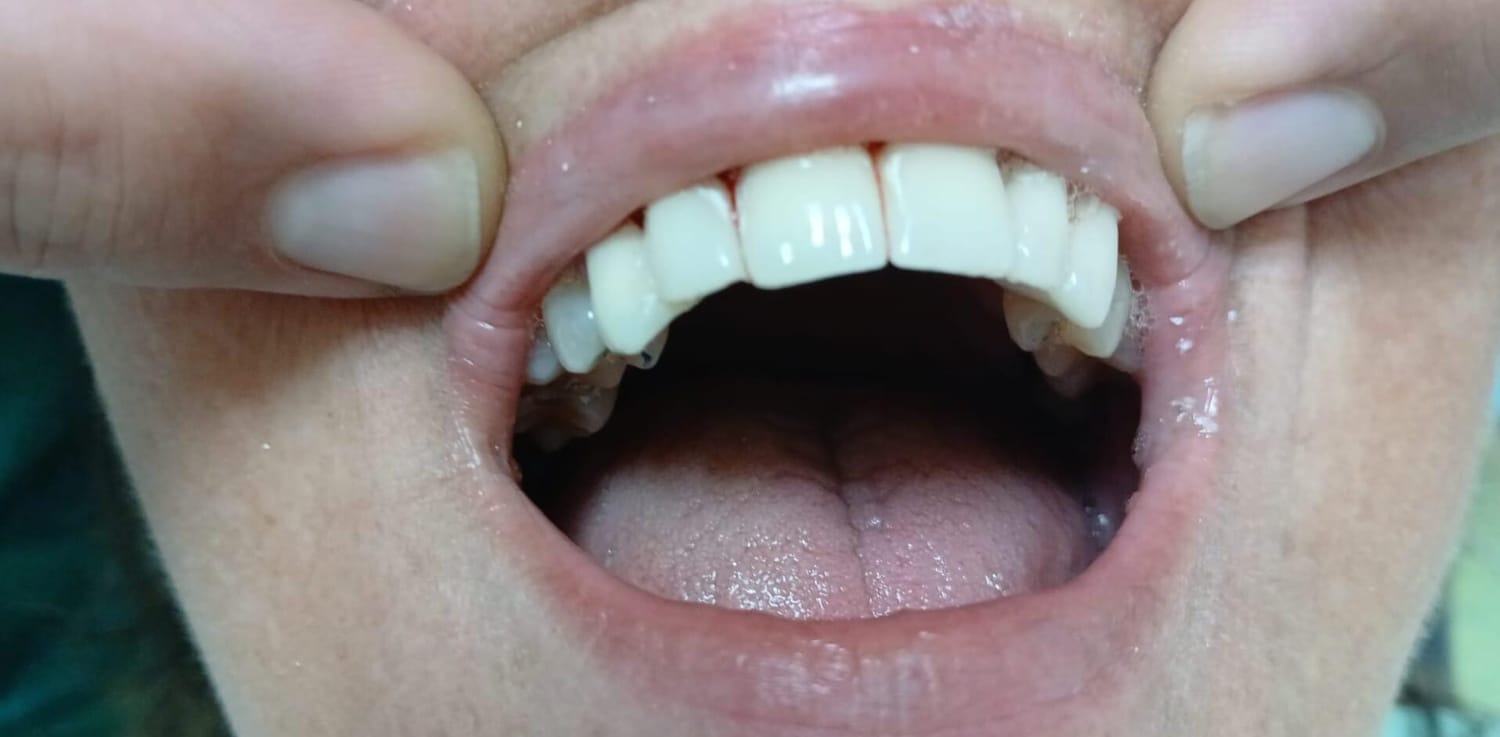

Paziente affetto da atrofia grave con parodontite acuta localizzata.

Caso progettato e realizzato attraverso la tecnica dell'implatologia computer-guidata con impianti short.

✅ Materiali di ultima generazione e un risultato dal 100% effetto naturale.